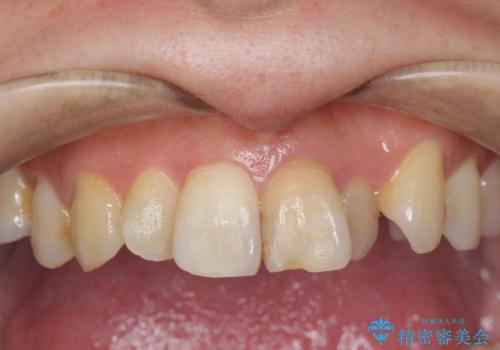

歯の変色 前歯の審美改善